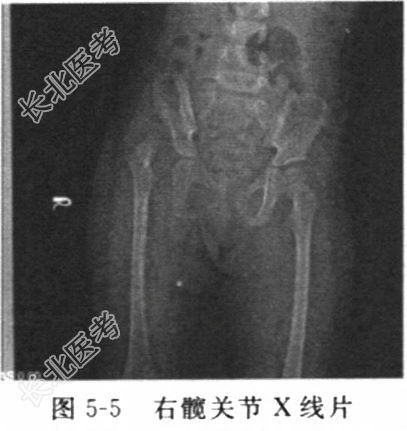

- [材料题] 患儿女性,2岁7个月,以“发现跛行10个月”为诉入院。缘于10个月前患者家属无意间发现患儿跛行,双下肢不等长,否认发热、畏寒,否认咳嗽、盗汗,否认有外伤,否认有难产、缺氧窒息,曾就诊外院拍X线片显示右髋关节发育异常,为求进一步治疗,转诊我院,门诊拟“先天性右髋关节发育异常”收入住院。患儿自发病以来,精神、食欲正常,睡眠、大小便正常。患者既往体健,否认“心、肝、肺、脾、肾”等重要脏器疾病史。否认“结核、乙肝”等传染病史,否认药物、食物过敏史,否认输血、外伤、中毒及手术史。个人史:G1P1,足月顺产,出时体重3.8kg,Apgar评分10分,无畸形及出血。出生后母乳喂养,按时按计划添加辅食,智力发育正常,2个月会抬头,1岁2个月开始行走,母妊娠期体健,无感染、发热史,无药物过敏及外伤等病史。家族史:父母非近亲结婚,身体健康。家庭成员中无遗传病史,家庭环境、经济情况和住房条件一般,患儿由奶奶照管。体格检查:T36.3℃,P90次/分,R20次/分。神志清楚,心肺未见明显异常。腹平软,无压痛。专科检查:跛行步态,右侧臀纹加深,右股骨大转子突出、上移、股骨三角空虚而凹陷,右股动脉搏动减弱,右髋内收肌紧张,髖关节外展受限,Allis征阳性,特伦德伦保(Trendelenburg)试验阳性,右下肢短缩2cm,脊柱生理弯曲存在,无畸形,棘突无压痛、叩击痛,运动自如,余肢体未见明显异常。辅助检查:右髋关节X线片(图5-5)示右股骨头发育小,右股骨上段向外侧移位,右侧Shenton线不连续,髖白变浅,右髖白角32°,左髖未见明显异常。